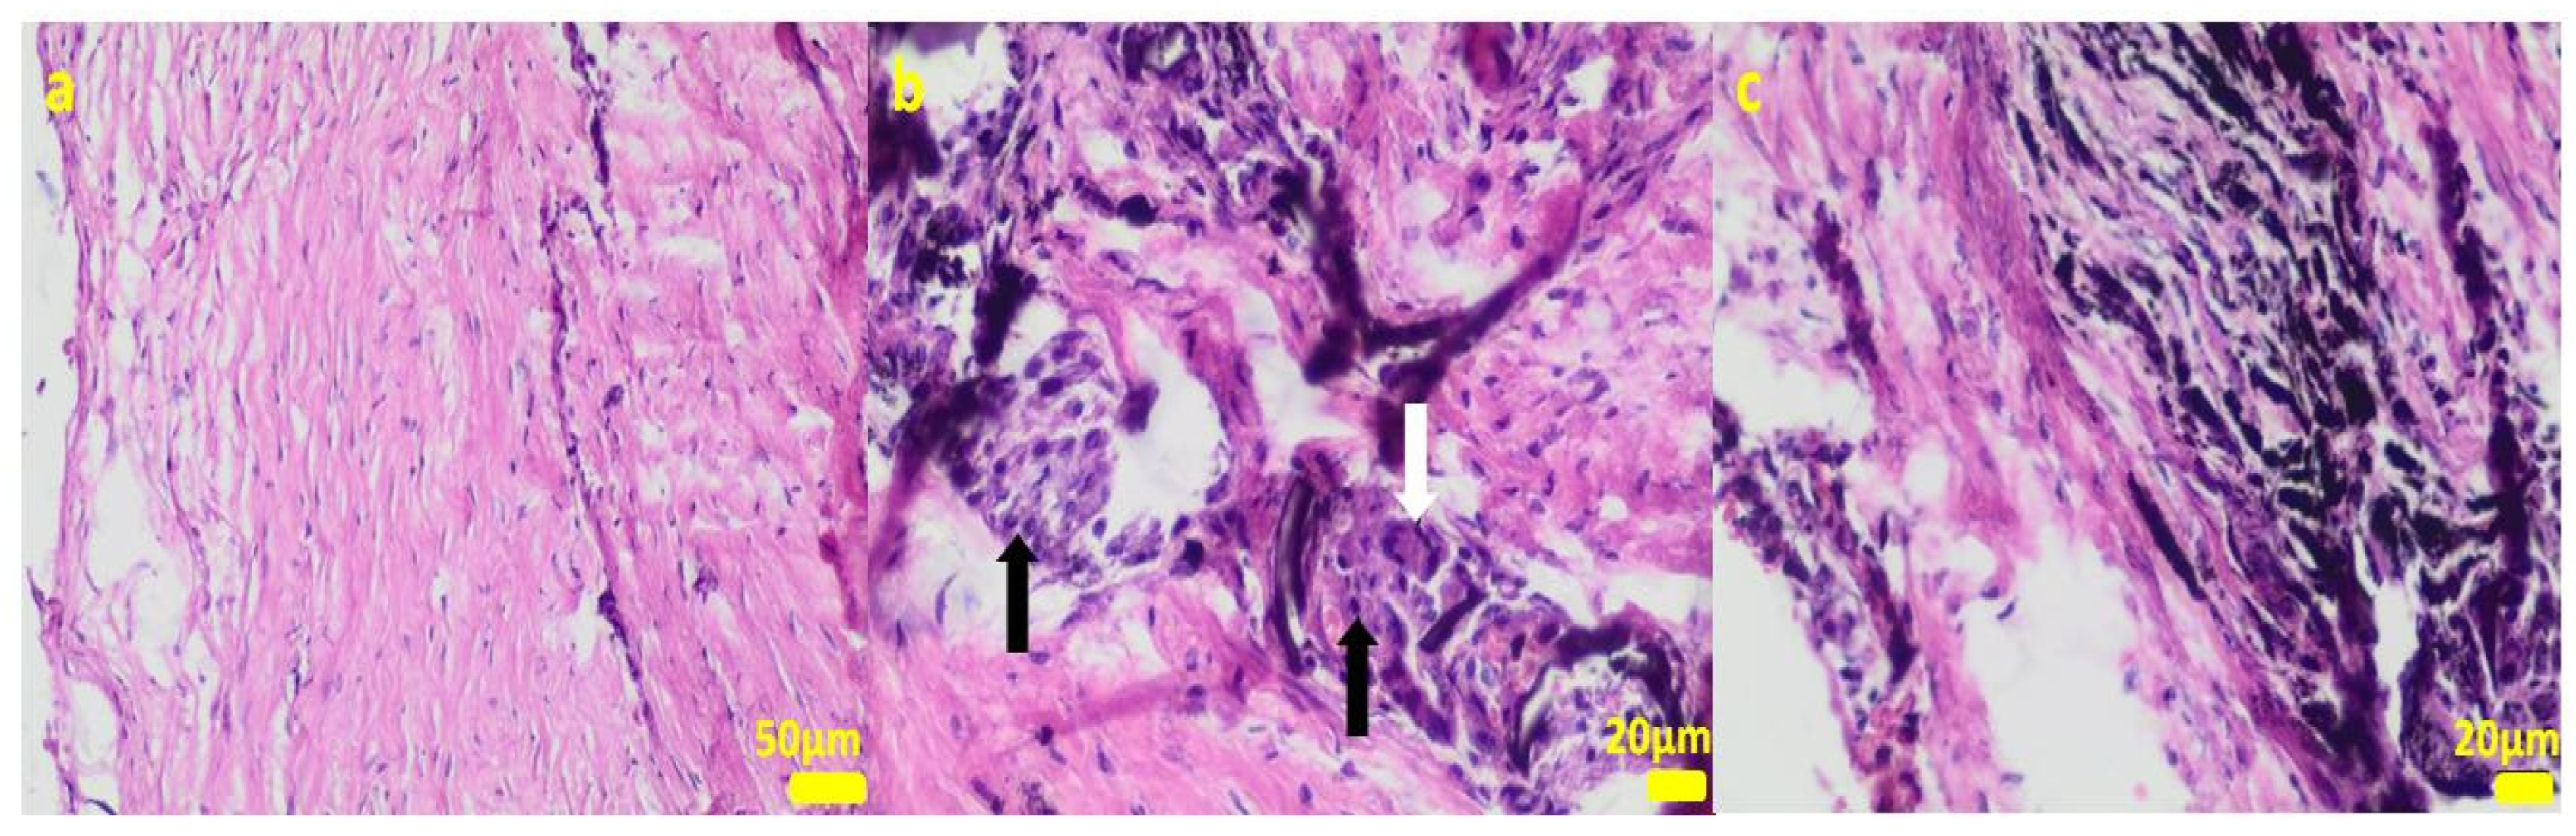

During the removal procedure, the implant proved to be very well-adhered to the tissue. The microscopic examinations of the collected samples (all the tissues collected after 3 months of implantations from the implant/bone contact area; each sample from the different patient) did not reveal microorganisms. Moreover, there was no inflammatory response suggesting a bacterial infection (Figure 6, Figure 7, Figure 8, Figure 9 and Figure 10). Although inflammatory infiltrates were found, they were more typical for a foreign body reaction (granulomatous inflammation in sample 1) or a chronic antigenic stimulation (plasmocytic infiltrate in sample 6).

Figure 6.

Sample 1:fibrous connective tissue (a) with small foci of inflammatory infiltrates consisting of macrophages (black arrows) including multinucleated giant cells (white arrow; (b)) and accumulation of fine fibrillar material and black pigment (c). Hematoxylin-eosin staining, magnification 400× (b,c), 200× (a).

The microscopic lesions observed in the examined samples suggested the correct tissue reparation process, starting from the granulation tissue up to the mature compact fibrous tissue that is typical for postsurgical scars. The implant, i.e., the TPLO plate and screws covered in the hybrid layer containing silver nanoparticles, seemed to facilitate the healing process; therefore, some features of granulomatous inflammation and plasmocytic perivascular infiltrates were present in the examined samples. Generally, both such microscopic findings and soft tissue calcification processes are observed in a natural healing process.